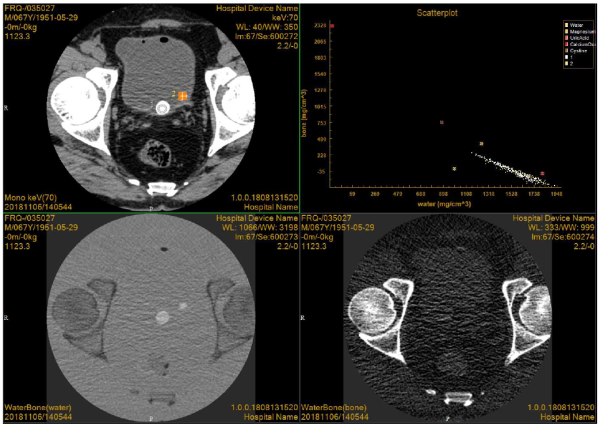

CT能谱成像是一种新兴技术,最早产生于20世纪70年代,但由于受到软硬件的限制而未能广泛应用。21世纪出现的以双kV为核心技术的能谱CT图像,为能谱成像的临床应用与研究创造了可能性。能谱CT是利用物质在不同X射线能量下产生的不同的吸收来提供比常规CT更多的影像信息的CT。与常规的单参数CT图像相比,能谱CT成像拥有涵盖多参数、定量分析的全新成像模式。

Precision 32精密断层能谱CT首次将目前高端CT具备的能谱成像技术广泛应用到32层CT,对常规CT难以定性的病灶和组织进行定性诊断和定量分析,提高诊断的精确度和安全性,将CT影像诊断成功率提升到一个全新的高度。